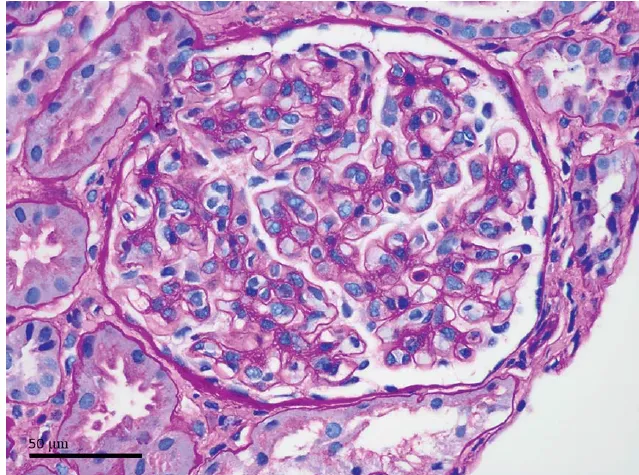

DRC indeterminada ou você esqueceu de fazer o básico? Veja tudo aqui

DRC indeterminada ou você esqueceu de fazer o básico? Veja tudo aqui